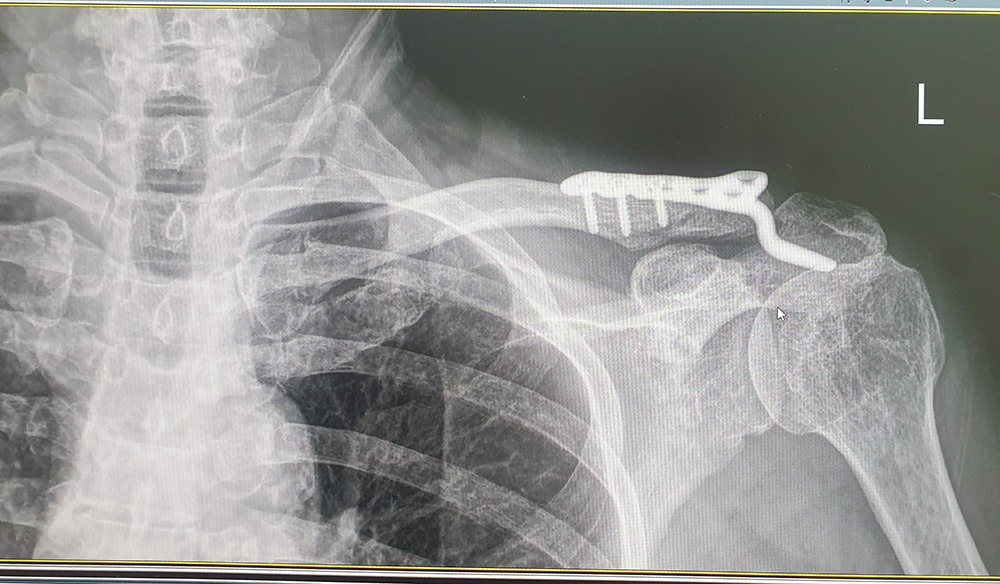

수술후 쇄골뼈 사진 나는 회복에 들어오면서 용광로를 통과하는 듯한 시련과 고통을 겪었다. 용광로는 뜨거운 열기와 압력으로 나를 고통스럽게 하였다. 무릎 연골이 터졌다. 뭔가 잘못되어 2번 수술을 받았다. 심지어 성남으로 이사 온 다음날 출근길에서는 버스 안에서 버스가 급정거하는 바람에 중심을 잡지 못한 나는 붕 떠서 떨어지면서 고관절 골절상을 당했다. 철심을 박아 잘 붙어가던 뼈는 ‘무혈성 괴사’라는 증상이 와 인공관절로 바꾸는 수술을 해야 했다. 고관절이 아파서 절뚝거리고 다니니 몸에 균형에 깨져 ‘구안와사’가 왔고 안구 앞부분의 일부만 붙어있어서 안구 내의 유리체를 빼내고 인공유리체로 교체하는 수술을 받기도 했다.